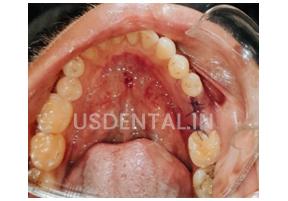

Here are the pictures after placing the implant.

After completion of the healing period, we took the measurement for the final implant crown. And cement kept PFM implant crown with access hole was luted with cement.

Patient was called to come for follow-up after 10 days. Patient was happy and satisfied as he did not feel discomfort on chewing and the crown was looking more natural and chewing has become easier than before.